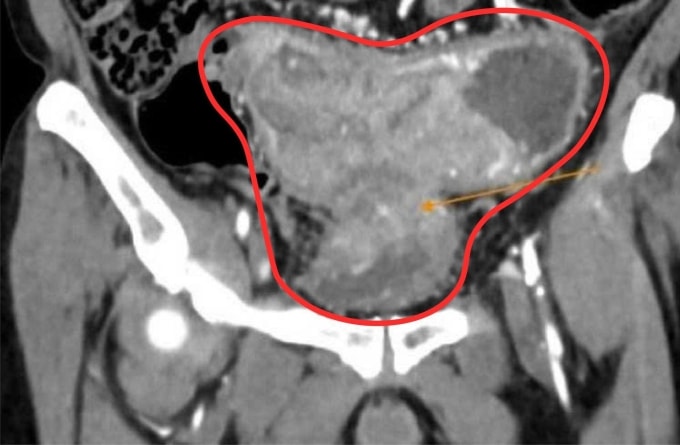

Ông về nhà uống thuốc nam theo liều lượng mỗi ngày ba bát thuốc sắc, kiêng ăn thịt. Táo bón ngày càng nặng hơn, ông sụt 15 kg, không ăn uống được, đau chướng bụng. 6 tháng sau, ông quay lại bệnh viện, chụp CT bụng ghi nhận khối u ác tính gây hẹp hoàn toàn lòng ruột dẫn đến ứ phân, dày thành bàng quang. Gan có hai tổn thương do u đại tràng di căn đến.

BS.CKII Nguyễn Trần Anh Thư, khoa Ung Bướu chẩn đoán ông Minh bị ung thư đại tràng sigma (đoạn ruột cuối cùng, có hình chữ S trước khi nối với trực tràng) giai đoạn 4, xâm lấn bàng quang, di căn gan. Ông Minh được phẫu thuật nội soi làm hậu môn nhân tạo, tiếp đến dùng thuốc trúng đích kết hợp hóa trị theo phác đồ FOLFOX (phối hợp ba loại thuốc).